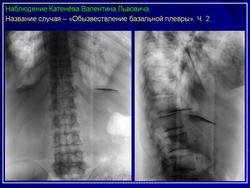

Плевральная кальцификация.

Продолжение.